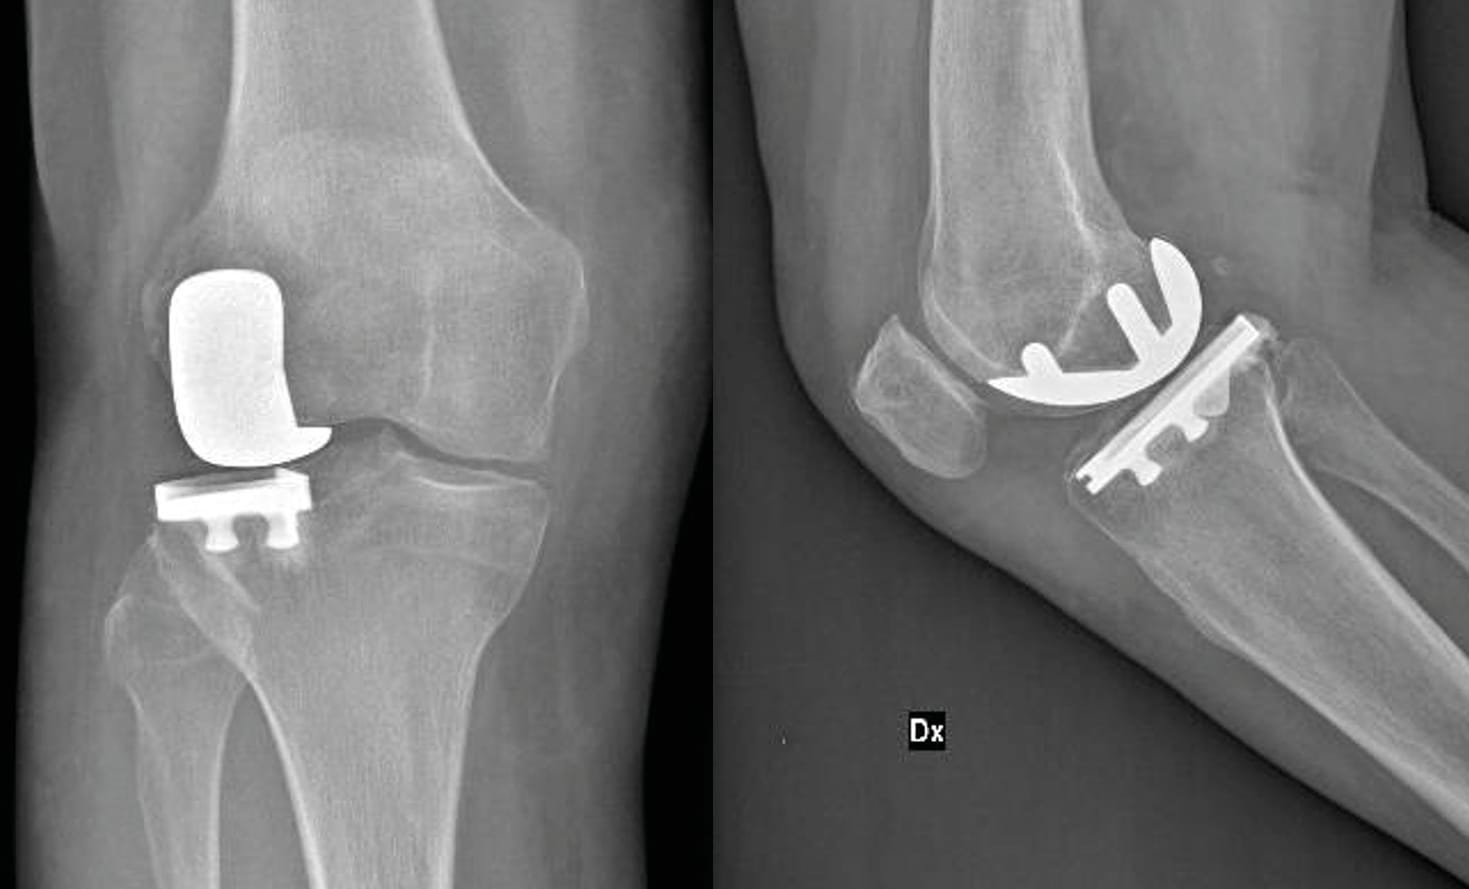

Unicompartmental knee arthroplasty (UKA) has emerged as a compelling alternative to total knee arthroplasty (TKA) in managing arthritis localized to the lateral compartment of the knee. Specifically, for patients with osteoarthritis confined to the lateral compartment, lateral UKA represents a viable treatment option, provided appropriate patient selection criteria are adhered to. In contrast to TKA, UKA offers numerous advantages, including a bone-conserving and ligament-sparing surgical approach, expedited recovery, enhanced range of motion, improved functional outcomes, and reduced hospital stays (Figure 2).

Despite these benefits, UKA procedures remain relatively uncommon, comprising only a small fraction (8–12%) of knee arthroplasties, with a mere 10% addressing the lateral compartment. Several factors contribute to this discrepancy. Firstly, lateral osteoarthritis is less prevalent, affecting approximately 1% of the population compared to its medial counterpart. Moreover, distinct anatomic and kinematic disparities exist between the medial and lateral compartments, such as increased laxity, smaller anteroposterior dimensions, and greater mediolateral length, posing unique challenges for UKA designs. Consequently, certain UKA designs exhibit reduced adaptability and a heightened incidence of bearing dislocation, particularly in the context of mobile-bearing lateral UKA, thereby diminishing confidence in lateral UKA procedures.